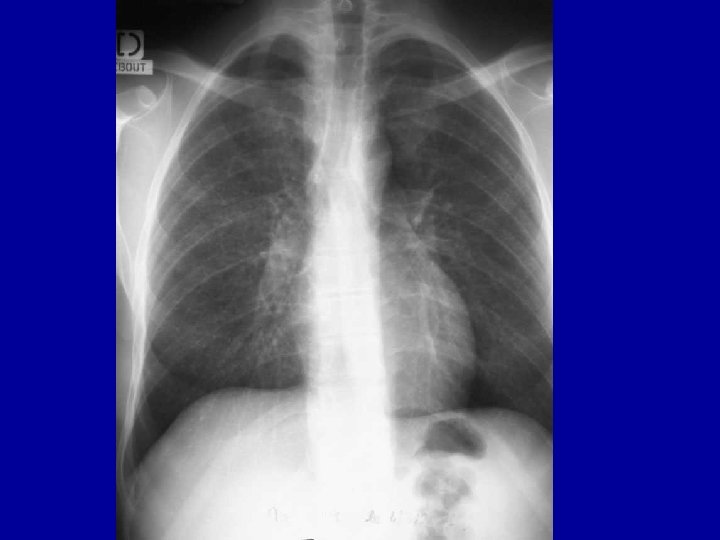

Les complications graves : SIDA • La pneumocystose – Infection pulmonaire – Clinique • En général apparition progressive • Dyspnée, toux • Image pulmonaire – Diagnostic : lavage broncho-alvéolaire – Peut être grave • mortalité 100% en l’absence de soins – Thérapeutique disponible • Triméthoprime-Sulfaméthoxazole – Fortes doses – Risques d’intolérance – Prophylaxie secondaire nécessaire (TMP-SMX)